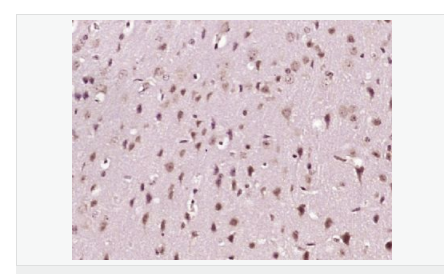

| 產(chǎn)品應用 | WB=1:500-2000 IHC-P=1:100-500 IHC-F=1:100-500 ICC=1:100-500 IF=1:100-500 (石蠟切片需做抗原修復) not yet tested in other applications. optimal dilutions/concentrations should be determined by the end user. |